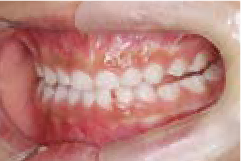

出っ歯

あごや骨格を正しく成長させる矯正治療

Aさん (矯正開始時:8歳)

Before

After

鼻がつまりやすく、口呼吸をしているために上あごが狭い状態でした。また上の前歯がかなり前へ傾いているため、お口をきちんと閉じていることができません。さらに、下の前歯もでこぼこしていました。

治療を終えて

装置によって上あごを拡大し、下あごを少し前へ成長させたことで、永久歯がきれいに並ぶスペースを確保しました。また、お口の機能が向上したことから鼻がよく通るようになり、口呼吸も改善され口も閉じやすくなったので顔の表情もよくなりました。

主訴・治療内容 下あごが後ろに下がり、出っ歯のようになっていることを心配して、無料相談に来院されました。

治療期間 2年半

費用 462,000円(税込)